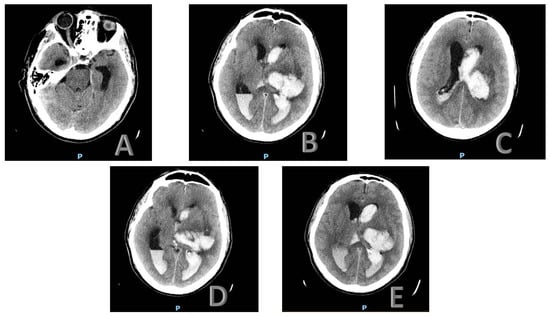

Upon reassessment a few days later, following a new brain CT scan, the intraparenchymal hemorrhage remained stable, localized in the left nucleus-capsular region and extending to the corona radiata and semioval center. However, the perilesional edematous halo had slightly increased, resulting in a modest worsening of the contralateral midline shift, now estimated at approximately 9 mm. The subarachnoid hemorrhage in the right parietal region remained unchanged, while a slight reduction in the intraventricular hemorrhage volume was observed, particularly in the fourth ventricle (Figure 1A–E).

Figure 1.

Imaging of the patient’s brain CT scan. Letters A through E show different levels of scanning: (A) Axial CT scan showing a hyperdense lesion in the posterior fossa, suggestive of acute hemorrhage. (B) Axial CT scan revealing intraventricular hemorrhage with blood layering in the lateral ventricles. (C) Axial CT scan demonstrating significant intraventricular hemorrhage with hydrocephalus. (D) Axial CT scan showing progression of hemorrhage with ventricular dilation. (E) Axial CT scan illustrating extensive intraventricular hemorrhage with midline shift and severe hydrocephalus. P: posterior.